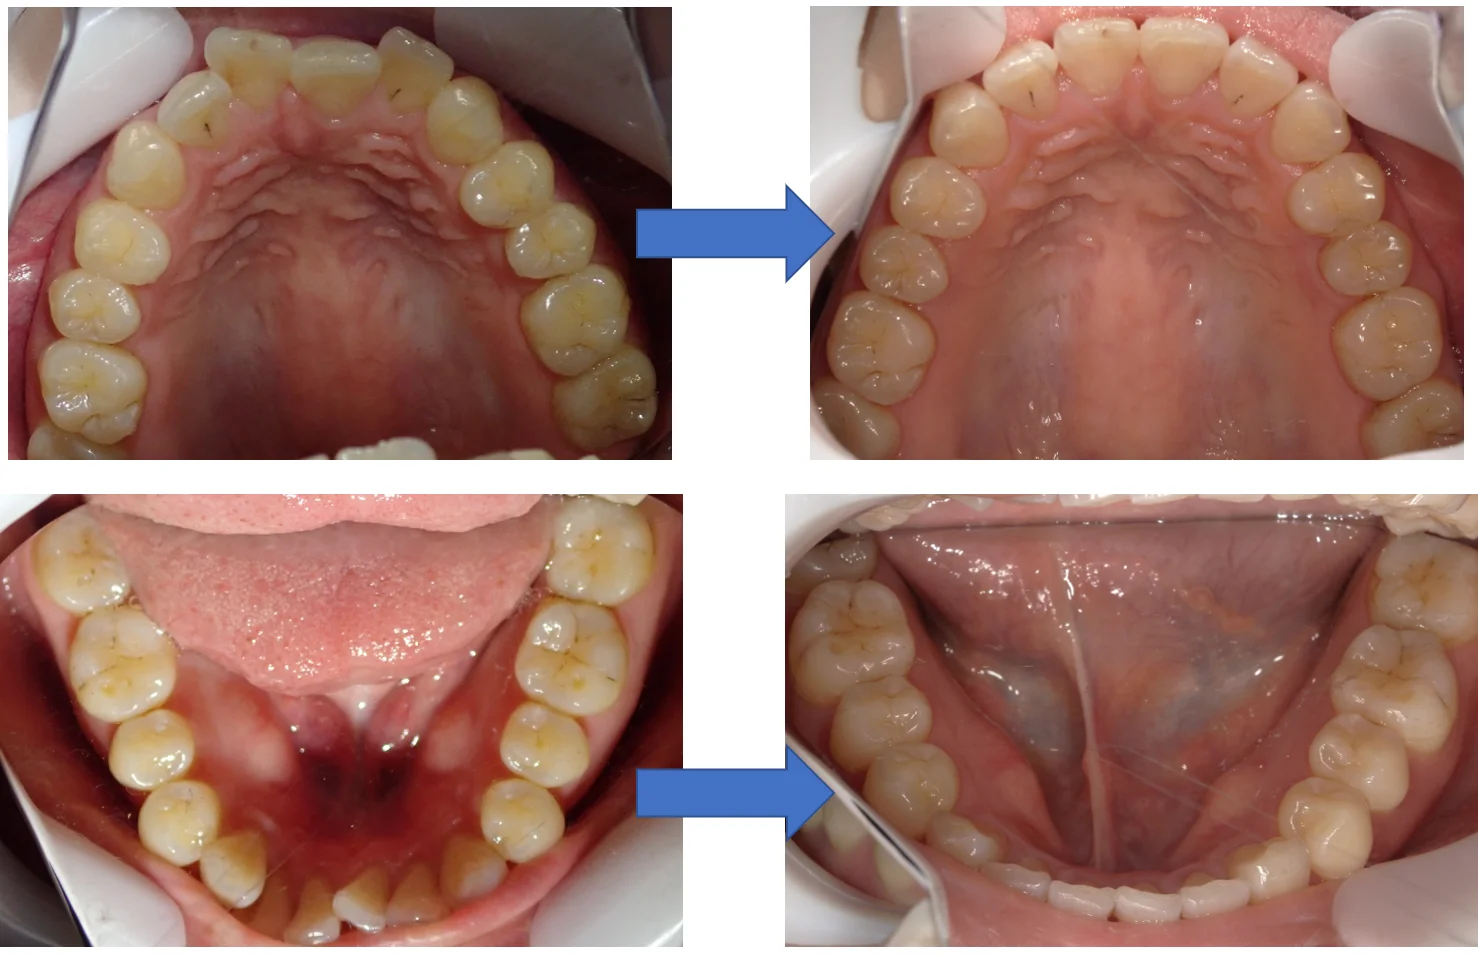

ダイレクトボンディングによる治療

まだ坂寄歯科医院には全顎的にダイレクトボンディングで治療した症例がありませんので、前の医院にて治療を完了された方の写真を載せたいと思います。 写真が下手なのは勘弁してください・・・。 鏡面像で反転済みです。 「向こう側からこちらに向かって口…

続きを読む →